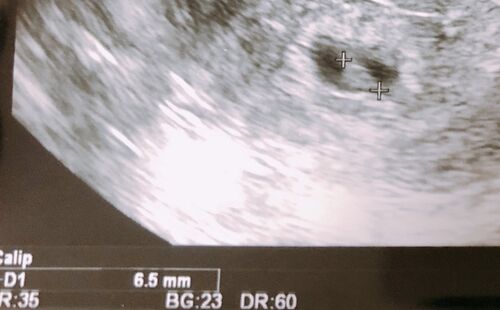

みなとみらい夢クリニック 凍結分割胚移植周期 1回目 ET34(D50) 移植後の通院 内診+診察 心拍確認の日

今日は、移植後4回目の通院です。 心拍確認の日です。 今日は待ち時間が長かった~!! 夢クリに2時間半いました。 心拍確認までくると採血もないみたいです。 つわりもないし、なんか、またダメな気がしちゃいます。 流産確定になると思っているので帰りは…